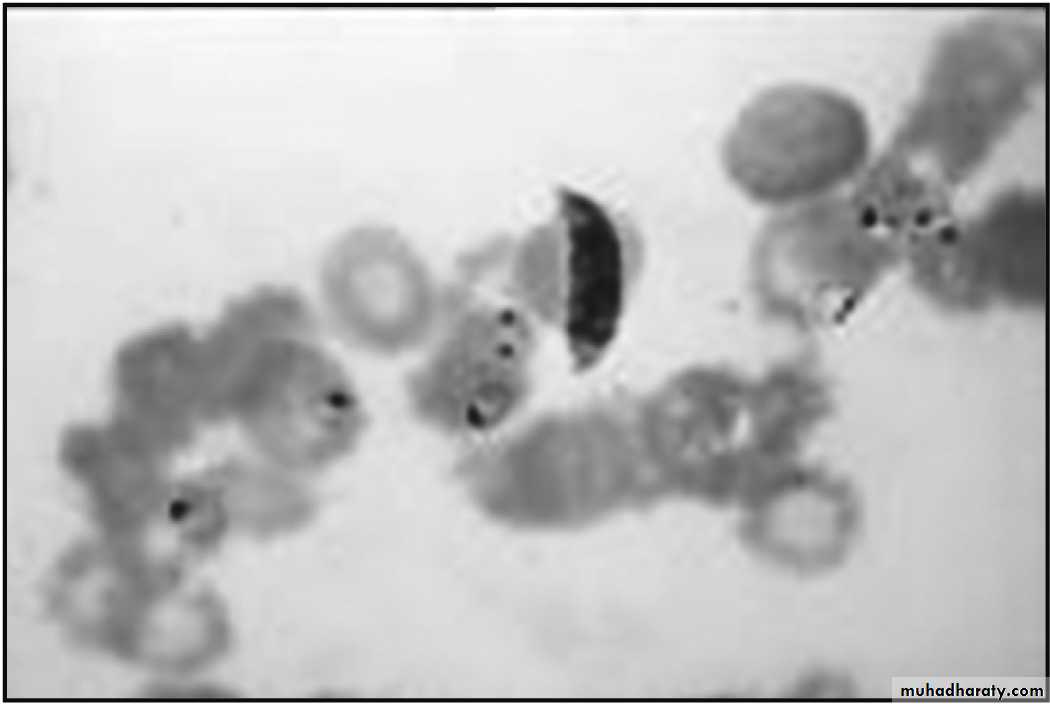

Giemsa stained smear: ring form and gametocytes of Plasmodium falciparum

14In the peripheral smear all the stages of the parasite are seen. These include the trophozoite form, schizont form and the gametocyte form.

• The ring form (trophozoite form):

• Note infected red cell is larger than uninfected red cell.15

Early ring form: P vivax

ii- Growing trophozoite: “Amoeboid form” with “pseudopodia-like” cytoplasmic extension. Note infected red cell is larger than uninfected red cell. Schuffner’s dots appear as fine reddish dots on infected red cell membrane

“Amoeboid form”Schüffner's dots

(b) Schizont:• Immature schizont: has 2-24 nuclei. Schuffner’s dots appear as fine reddish dots on infected red cell membrane. Infected red cell become irregular in shape and pale in color and enlarged.

(ii) Mature schizont: containing 12-24 merozoites. Schuffner’s dots appear as fine reddish dots on infected red cell membrane.

Immature Schizont

Mature Schizont